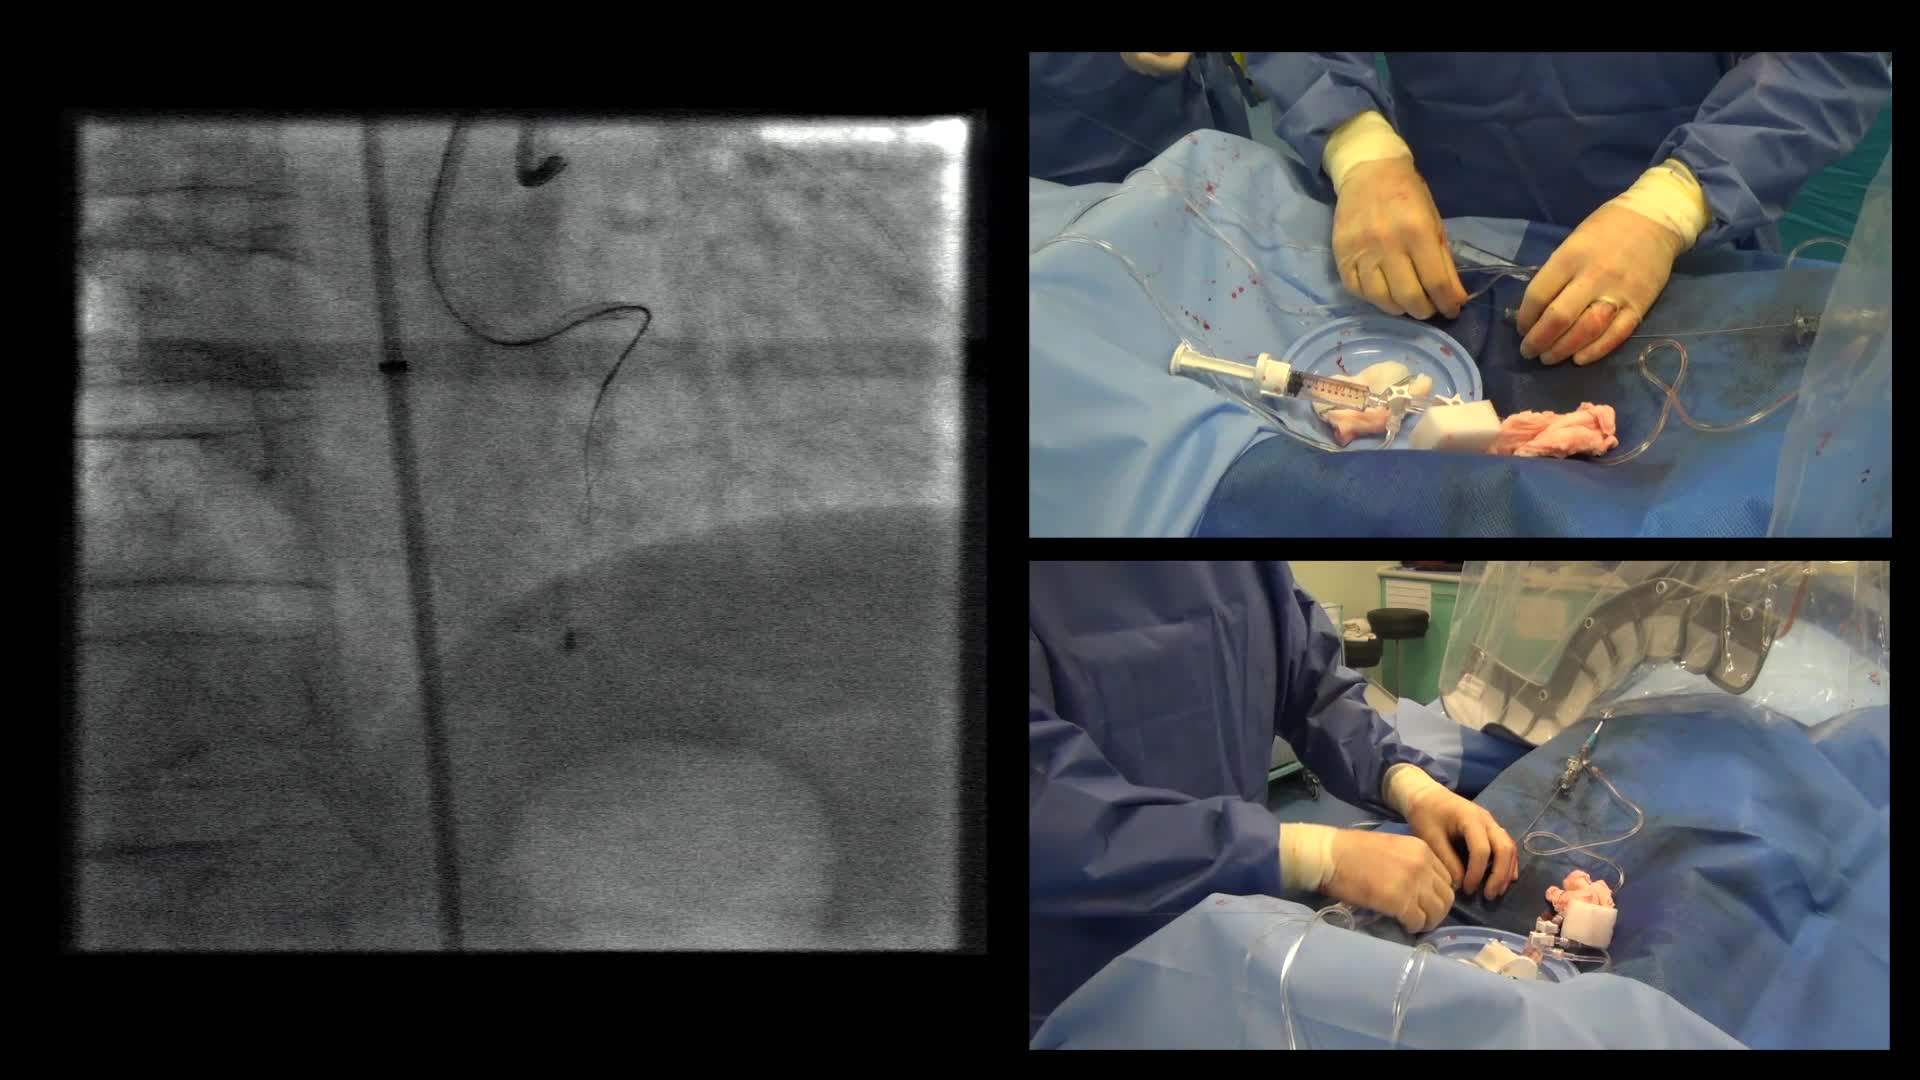

Case 1 - Antegrade Wire